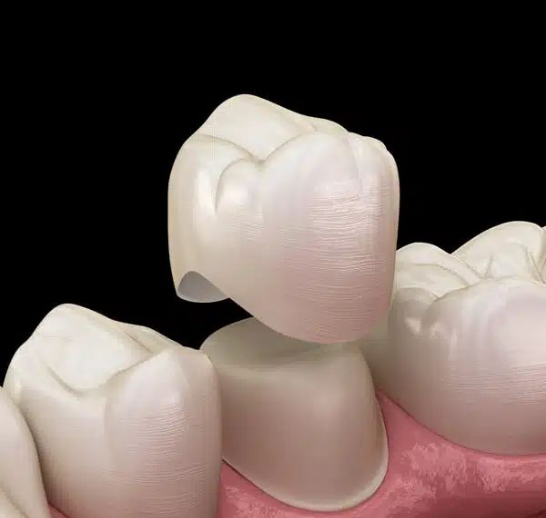

Types of Dental Crowns

- Porcelain Crowns – Natural-looking and stain-resistant

- Ceramic Crowns – Ideal for front teeth

- Zirconia Crowns – Strong and highly durable

- Porcelain Fused to Metal Crowns – Strength with aesthetics